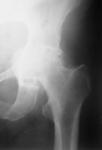

骨盆-双侧髋部前后位X线片(图1)和左侧髋部X片(图2),结果显示髋臼前突。临时诊断为强直性脊柱炎急性发作。

图2: